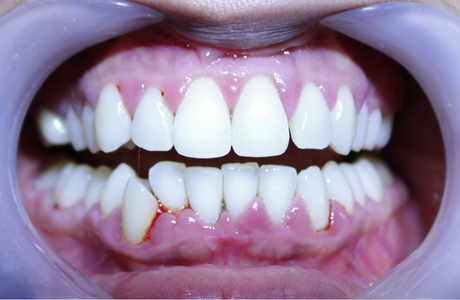

La gingivite est le premier stade de la maladie parodontale. La jonction gencive-dent est colonisée par des bactéries qui déclenchent une inflammation de la gencive. Rouge, gonflée et douloureuse, la gencive se décolle de la dent et le tartre s’accumule sous la gencive. A un stade avancé et en l’absence de traitement, la gingivite évolue en parodontite.

LA PARODONTITE

Au stade de la parodontite, la destruction porte alors sur l’os de la mâchoire et les ligaments de soutien qui ancrent les dents (ligament alvéolo dentaire). Des poches parodontales se forment et les bactéries s’y accumulent, avec plus ou moins de pus. A terme, le déchaussement de la dent peut amener la perte de celle-ci, accompagnée parfois d’une collection purulente très douloureuse.